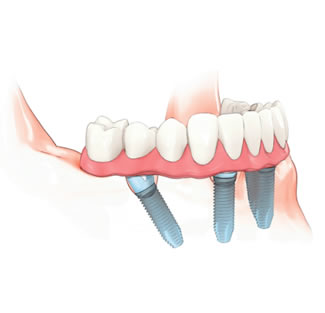

Desenho esquemático da prótese fixa com 12 dentes aparafusada em 48 horas após a instalação cirúrgica dos implantes:

Realizando de 4 a 8 implantes é possível adaptar com firmeza uma prótese fixa aparafusada sobre a maxila e ou mandibula. No máximo, em dois dias após a instalação cirúrgica do implantes o paciente recebe a prótese aparafusada.